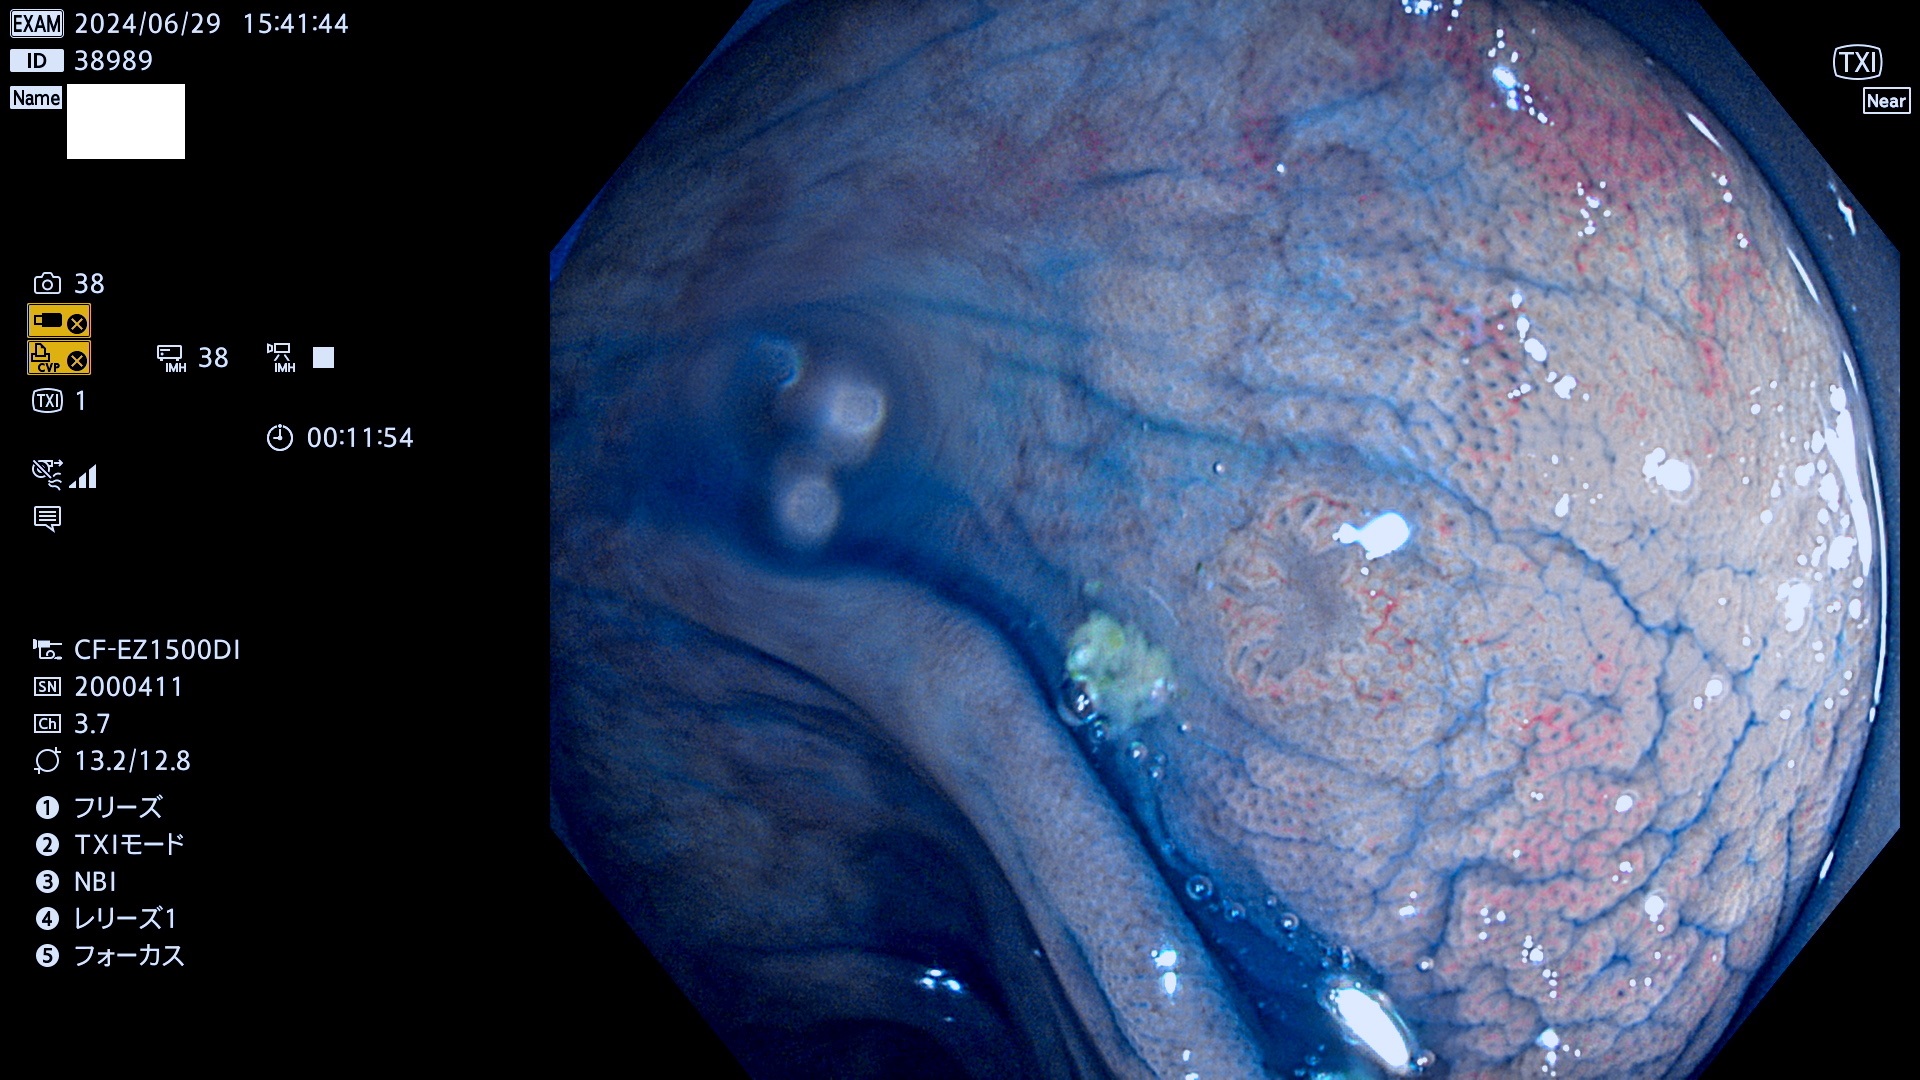

完全に平坦な物をUb、陥凹している物をUcと呼びます。最も発見が難しく危険な病変です。

抽出の対象期間 2024年6月27日〜7月1の5日間(40件の検査)6件 (6/40=15%)